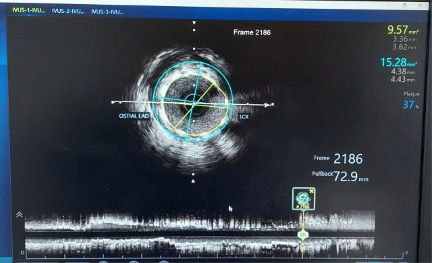

A coronary snare was used to retrieve the proximal segment of the retained wire. Partial extraction was achieved, but tangled wire fragments remained lodged in the proximal LAD. To stabilize these remnants, an additional DES was deployed to pin the wire against the vessel wall. Although angiography initially appeared satisfactory, intravascular ultrasound (OptiCross, Boston Scientific) proved pivotal by revealing that the wire loops had coiled within the stent, extended retrogradely into the proximal LAD, and reentered the stented segment near the left main stem (LMS) (Figures 2 [red arrow], 3A-C, Video 3).

A second DES (Resolute Onyx, Medtronic) was then deployed from the proximal LAD into the LMS, effectively jailing the wire fragments. IVUS assessment was performed from the ostial LAD (Figure 4A-C, Video 5).

Final angiography confirmed TIMI-3 flow with no dissection, perforation, or distal embolization; the wire in the side branch remained in place at the end of the procedure (Figures 2 [white arrow], 4A-C, 5, Video 6).